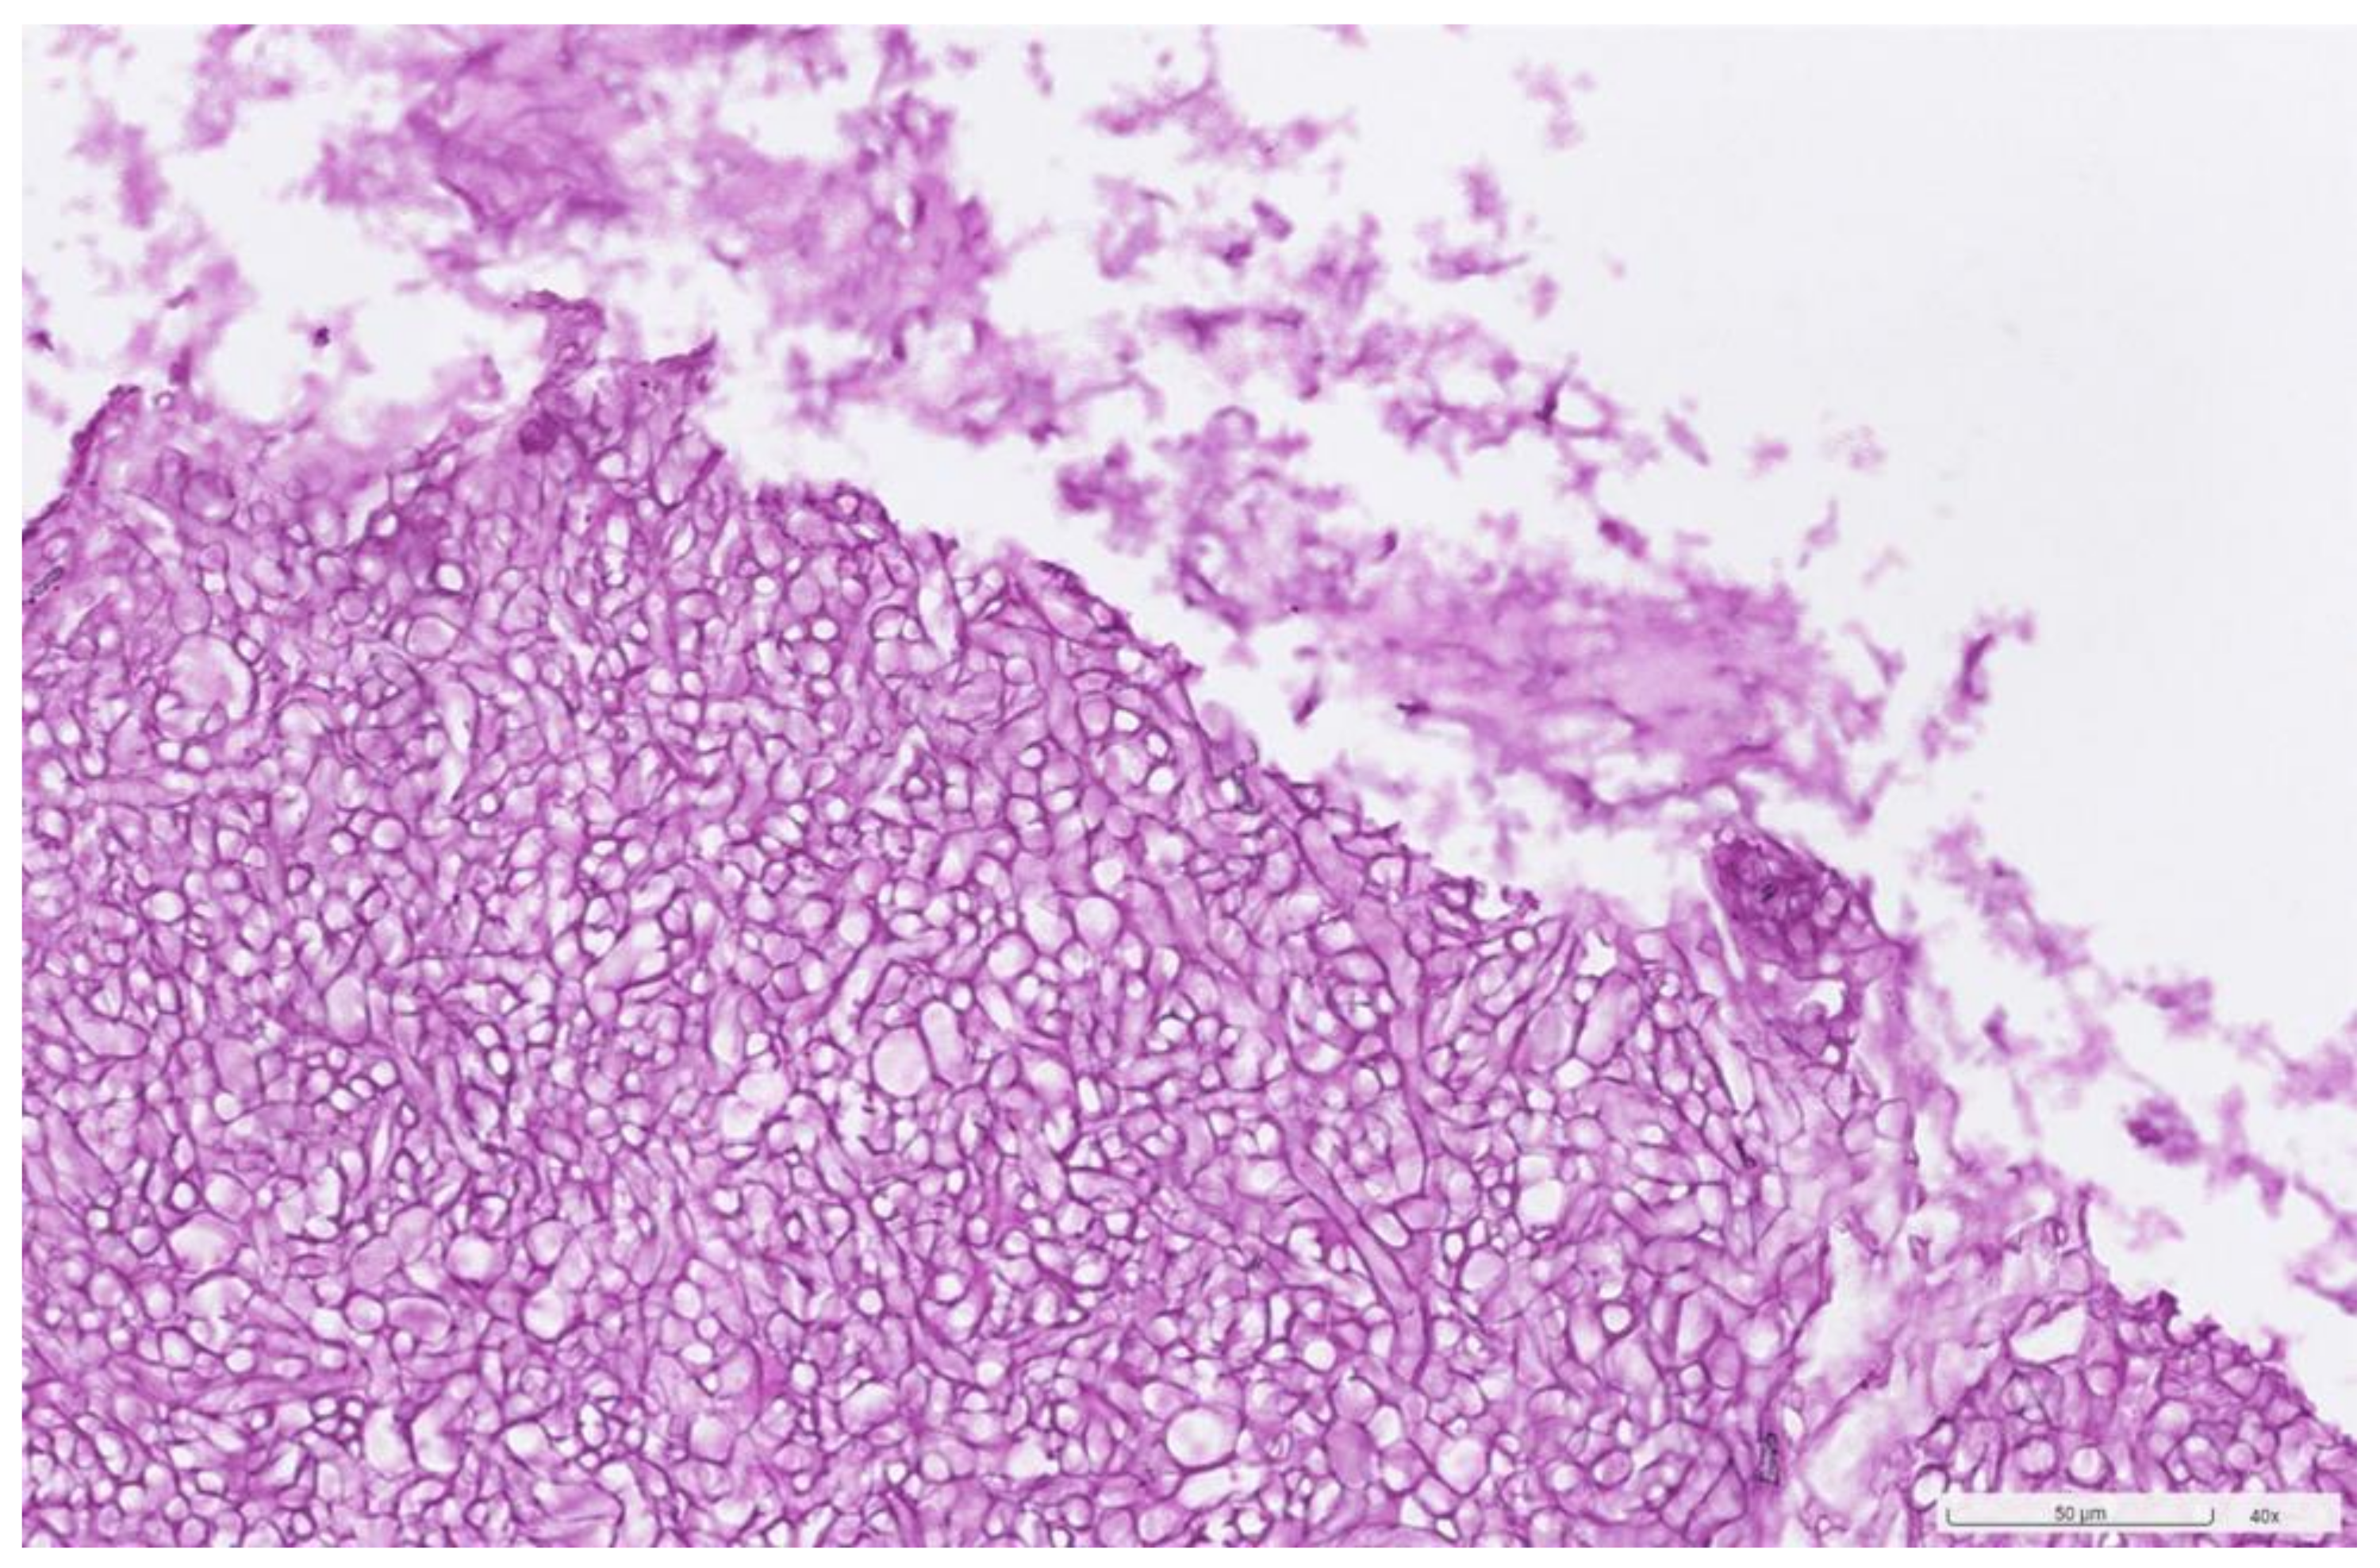

2. Case Presentation